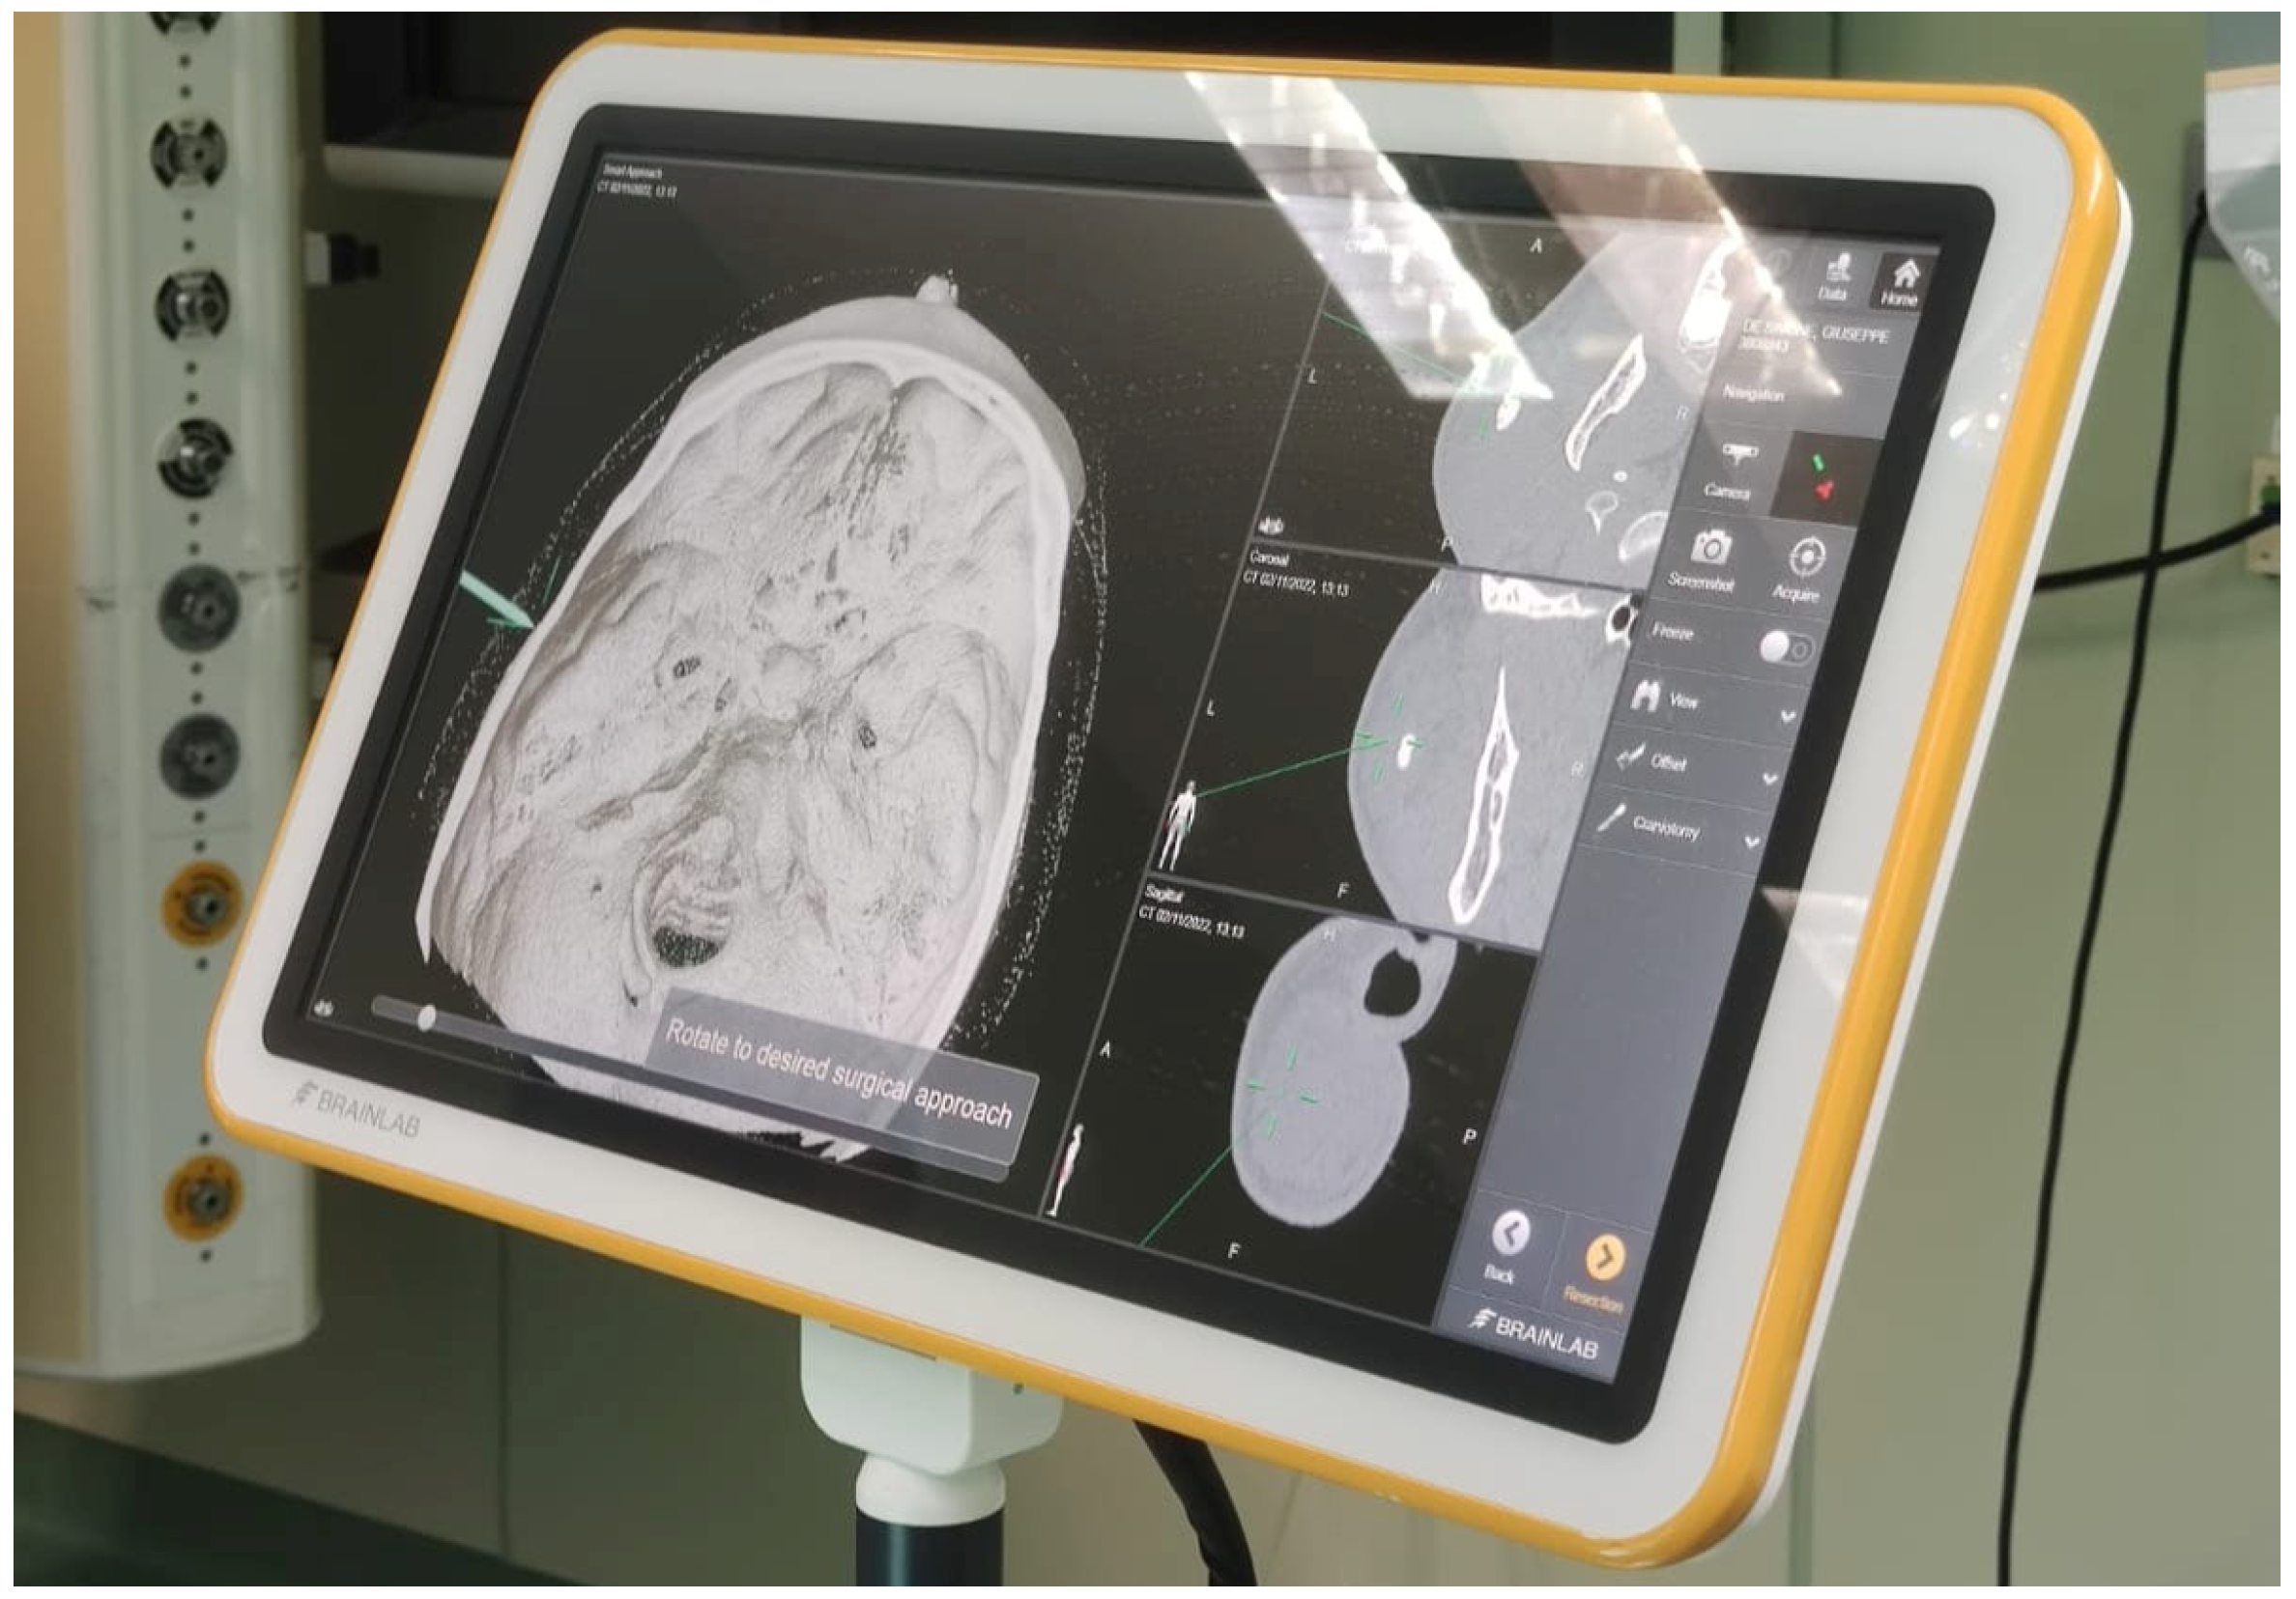

Before surgery, the patients’ digital imaging and communications in medicine data-set (DICOM) were imported on iPlan CMF 3.0 software (Brainlab, Munich, Germany) to set up the optical-based navigation system of the operating room (

Figure 1). A reference star array was attached to a headband on the head of the patients and a laser pointer was used to record landmark points on the face. During surgery, axial, coronal, and sagittal CT images, previously uploaded and reconstructed, were displayed on a kick display (Brainlab, Munich, Germany) to track the navigation pointer. The optical-based navigation was used to locate the stone (

Figure 2) and its position marked on the skin surface (

Figure 3). A preauricular skin incision was made, a skin flap was raised, and a blunt dissection, guided by the navigation system, allowed the exposure of the parotid gland and the subsequent exact localization of the stone as visualized on the display (